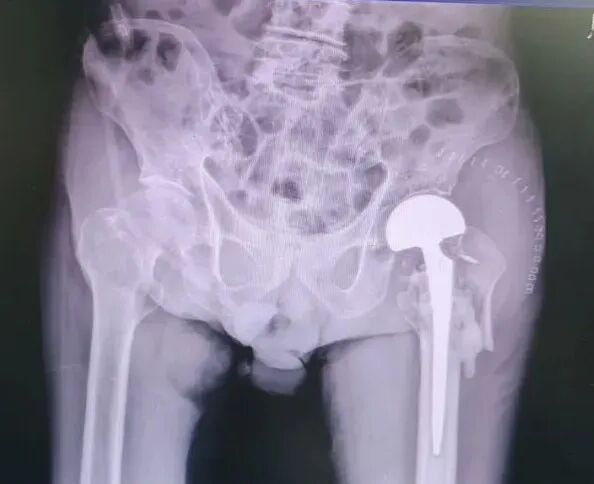

接诊后,骨科团队立即组织心内科、麻醉科、呼吸科等多学科专家进行联合会诊。专家们全面评估老人的身体状况,反复讨论手术方案,最终制定了创伤极小的人工股骨头置换方案,同时针对老人的心脏疾病制定了严密的围手术期监护和应急处理预案。

手术当天,麻醉团队凭借丰富的高龄患者麻醉经验,为老人实施了精准的麻醉;骨科手术团队仅用40分钟就顺利完成了手术。术后,护理团队为老人制定了个性化的护理康复方案,预防压疮,并根据老人心脏情况严格控制补液速度,指导进行下肢锻炼预防血栓,指导饮食,保证营养摄入,心理辅导,疏解不安。在医护人员的精心照料下,老人术后康复良好,顺利出院。